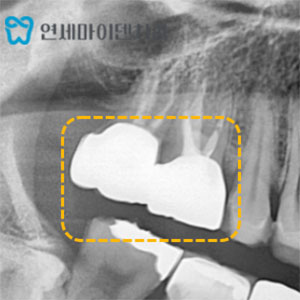

치료 사례